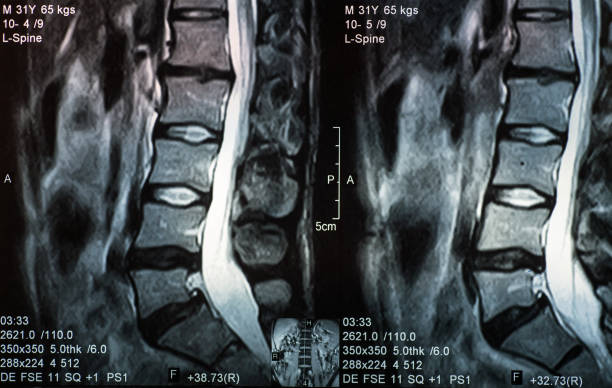

척추협착증은 척추의 추간공이 좁아져 척추 신경이 압박되는 질환입니다.

척추협착증의 증상이 심한 경우에는 수술 치료가 필요할 수 있습니다. 수술을 통해 추간공을 넓히고 압박을 완화시킴으로써 증상을 개선시킬 수 있습니다. 수술은 진통 및 통증 완화 효과가 높지만, 항상 최후의 수단으로 고려되어야 합니다.